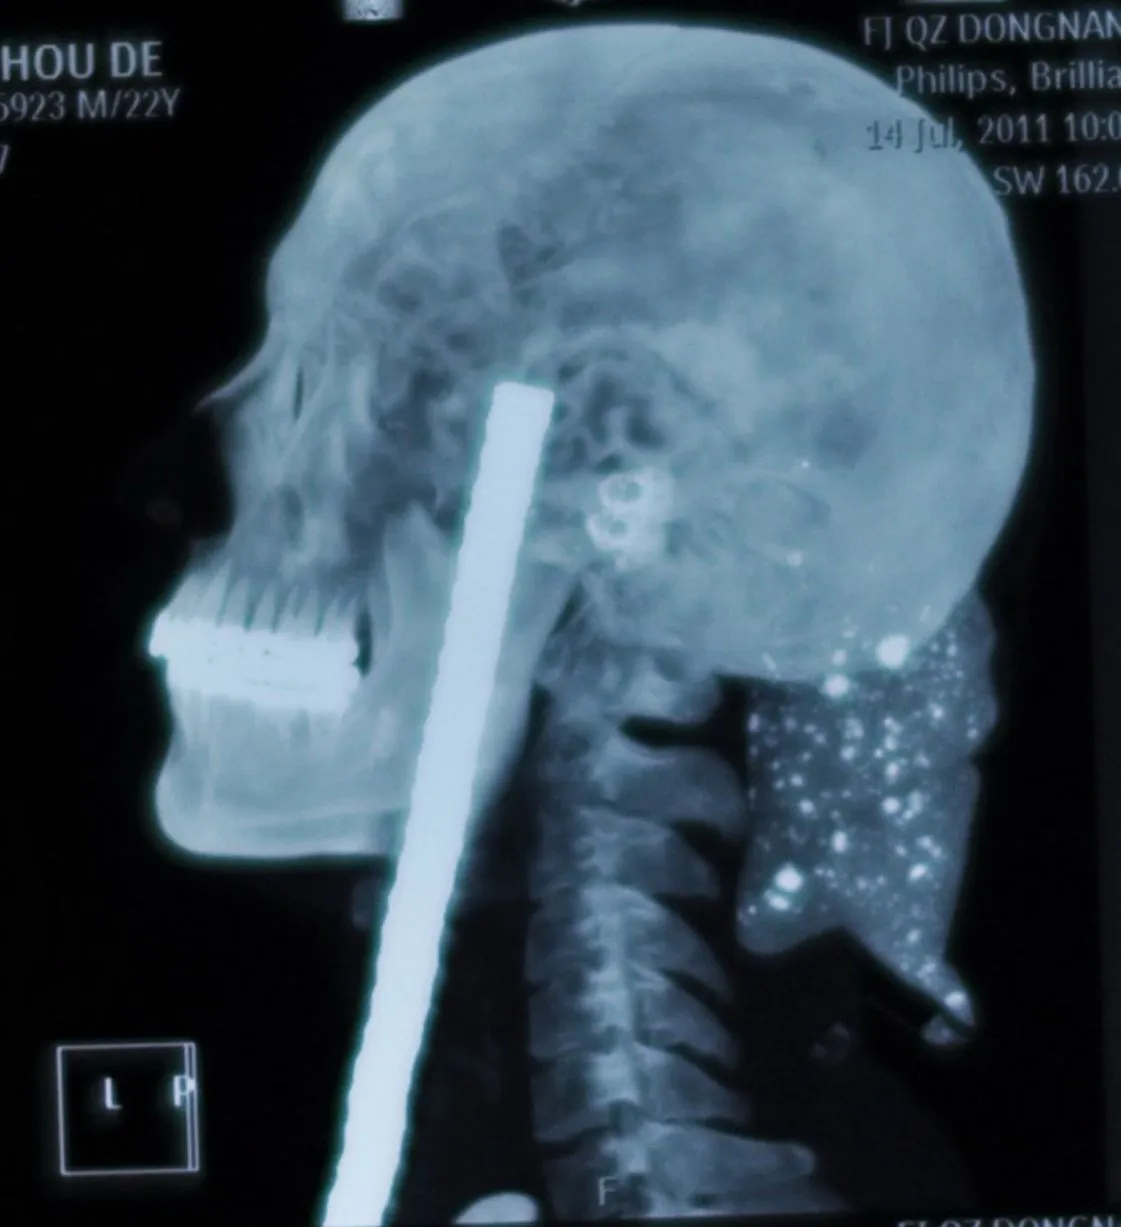

Jaw-dropping: A builder who took a tumble in China, Wu Moude, 22, landed on a steel bar which penetrated 15cm into his head from beneath his chin. It took five hours of surgery to remove the bar, which saw surgeons cut open Wu's windpipe and skull. (Photo by Rex Features)